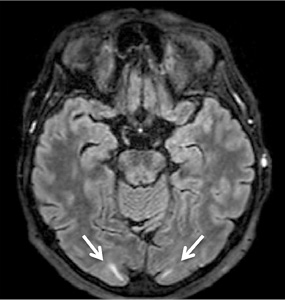

CT with venography, chest X-ray, abdominal US – no abnormalities. Awake EEG – no clear specific epileptiform activity observed. Sleep EEG (13th and 19th day) – bilaterally temporally, asynchronously connected, without a clear, stable dominant lateralization, single epileptiform potentials with peak wave morphology and slow (theta-delta) range episodes were recorded. Brain MRI – in bilateral occipital lobes, subcortically small hyperintense areas in T2W – mild PRES findings (Figure 2). |

On the third day of hospitalization, the patient experienced visual hallucinations and two additional generalized tonic-clonic seizures. MRI results revealed small subcortical hyperintense areas in the bilateral occipital lobes on T2-weighted images, which were moderately suggestive of PRES (Figure 2 and Table 2). There was no evidence of renal insufficiency, eclampsia, sepsis, allergies, autoimmune diseases, or the use of immunosuppressive or cytotoxic drugs. After managing the patient’s blood pressure, her condition began to improve: the visual hallucinations regressed, and no further seizure episodes occurred. Following treatment for GBS, muscle strength in the arms and legs improved. The patient was able to eat independently by using her left hand and sit up in bed.